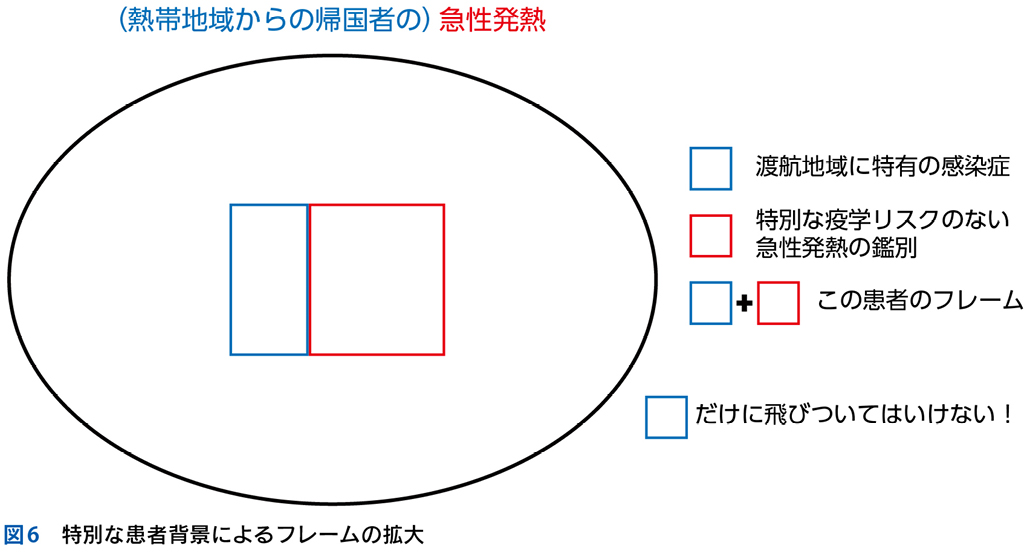

▶ むしろ,特別な患者背景(疫学的リスク)の存在はフレームを拡大するものとしてとらえるとよい。

▶ たとえば,発熱患者に最近の渡航歴があれば,一般的な(渡航と関係しない)発熱の原因疾患に加えて渡航関連感染症を考える。免疫抑制状態にあれば,日和見感染というフレームを追加する。特殊な背景がある場合,その背景に紐づくフレーム内に鑑別を限定するのではなく,一般的な患者で設定するフレームは保持したまま,そこに患者背景によるフレームを付け加えるようにすべきである(図6)。

▶ 筆者はこのタイプのSQによる診断の早期閉鎖を防ぐために,患者背景に当たる部分は問題を定義する上で( )つきで考えるようにしている(誤解のないように繰り返すが,基準率の推定は分析的診断の基礎なので,患者背景を正確にSQで表現することはきわめて重要かつ必須である)。